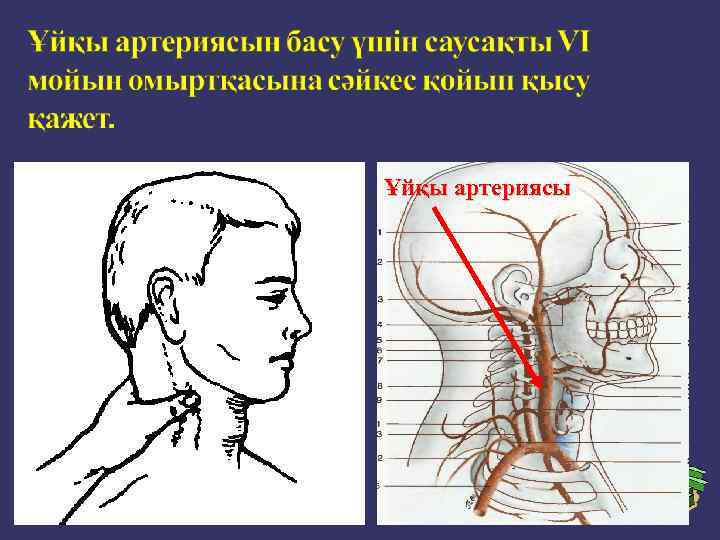

Кейбір қан тамырлардың жарақаттануы кезінде қанды тоқтату үшін ірі қан тамырларды сүйекке саусақпен басу қолданылады.

Ұйқы артериясы